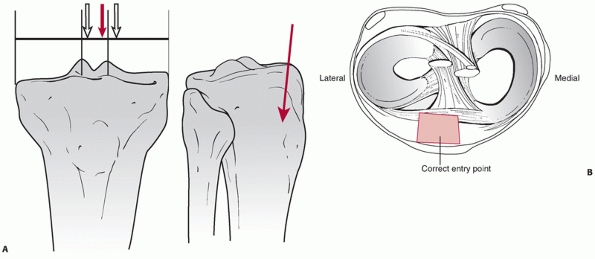

they can be placed using minimally invasive techniques and they can

span large areas of comminution as shown in Figure 55-11. Ricci et al.236

minimally invasive approach.236 All of the fractures united in satisfactory alignment.

![]() |

FIGURE 55-11 A. Anteroposterior and lateral radiographs of a comminuted proximal tibia fracture with an intra-articular extension. B. The fracture was successfully treated with a long locked plate and united uneventfully.